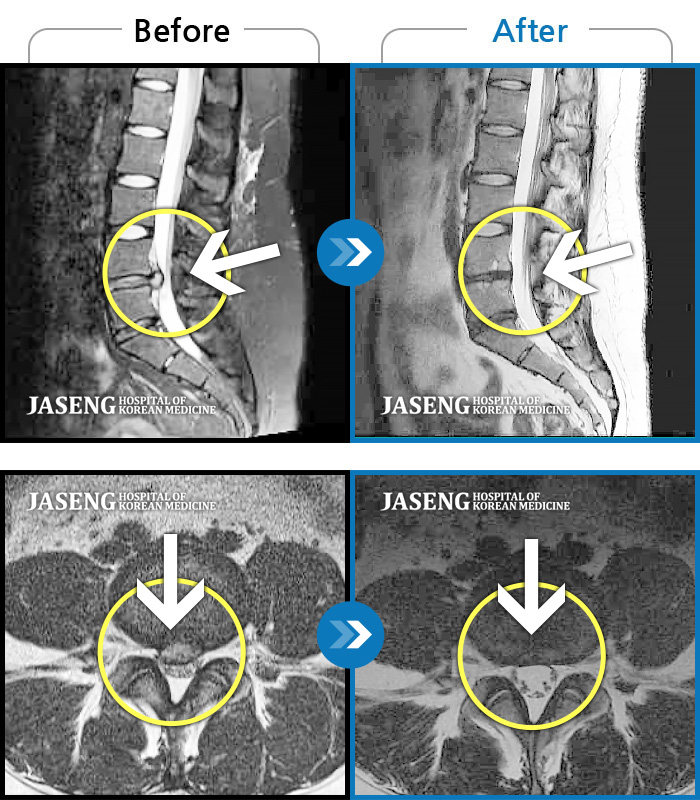

허리디스크

잠실 · 한상욱 원장

허리와 양 다리의 타는 통증으로 걷지 못한 상태로 내원

촬영시기

2021.04.08 ~ 2021.12.13

2021.12.23

조회수 92